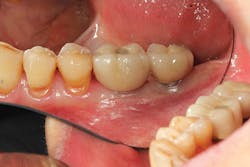

Implant manufacturing involves a high degree of precision. Implant fixture dimension, bone drill protocols, taps, and insertion devices should intimately correspond. Prosthetic components, abutment connections, and screws are also closely mated in design and production, so there is minimal tolerance between machined components. Interestingly, I hear much conversation regarding the poor fit of lower-tiered implant components, which can result in implant failure or screw loosening. Implant systems consist of CAD/CAM parts, with components that are fabricated with a high degree of homogeneity. Vertical and anti-rotational discrepancies exist and vary between companies and the types of connection used,12 but studies indicate that the fit of mismatched components improves with the application of mechanical torque to a clinically acceptable level.13 Clinicians also need to understand that there is more to screw loosening than the system-such as passive fit of the casting, proper torque values and preload,14 adequate interproximal contact, and the most often overlooked and misunderstood aspect of dentistry . . . occlusion (figures 7-9).

Figure 7

Figure 8

Figure 9

Figures 7-9: Implant site No. 19 has been restored for one year without any incident of screw loosening. Bone levels are excellent (figure 7), but a small gap is evident between the abutment and fixture platform upon radiographic evaluation (figure 8), due to the usage of implants from two "compatible" manufacturers. The tissue levels are excellent, despite a "mismatch" in components. Notice the gingival recession and the lack of attached tissue15,16 on distal implant site No. 18 (figure 9). However, with critical examination of implant No. 18, it is possible that the transmucosal element is too long and the overlying gingival tissues too thin, making this particular fixture inappropriate for this site. (Perhaps a bone-level fixture would have been a better choice.)